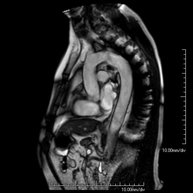

Prova diagnòstica no invasiva que consisteix en l'obtenció d'imatges d'alta definició anatòmica de l'abdomen mitjançant l'ús d'un camp electromagnètic i ones de ràdio (amb un emissor i un receptor). No utilitza radiació ionitzant. En aquesta exploració s'inclouen el fetge, el pàncrees, la melsa, la via biliar, la vesícula biliar, les glàndules suprarenals, els ronyons, l'aorta abdominal, la vena cava inferior, l'estómac, el duodè, etc. En alguns casos caldrà emprar contrast paramagnètic (Gadolini) per caracteritzar les lesions. - RM Pelvis femenina

Prova diagnòstica no invasiva que consisteix en l'obtenció d'imatges d'alta definició anatòmica de la pelvis mitjançant l'ús d'un camp electromagnètic i ones de ràdio (amb un emissor i un receptor). No utilitza radiació ionitzant. Es realitza per a l'estudi de patologies d'úter, d'ovari, de trompes i de vagina, ja siguin d'origen tumoral, inflamatori o vascular. També permet valorar les estructures adjacents localitzades a la pelvis i la identificació de les seves alteracions. De vegades és necessari l'ús de contrast intravenós (Gadolini) per caracteritzar les lesions. - RM Pelvis masculina

Prova diagnòstica no invasiva que consisteix en l'obtenció d'imatges d'alta definició anatòmica de la pelvis masculina mitjançant l'ús d'un camp electromagnètic i ones de ràdio (amb un emissor i un receptor). No utilitza radiació ionitzant. No requereix preparació prèvia. En algunes ocasions necessita l'ús de contrast paramagnètic (Gadolini) per caracteritzar les lesions. Aquesta prova permet valorar òrgans com la bufeta urinària, la unió entre els urèters i la bufeta, la pròstata, les vesícules seminals, la uretra i els ossos de la pelvis, entre d'altres. - RM de Fetge